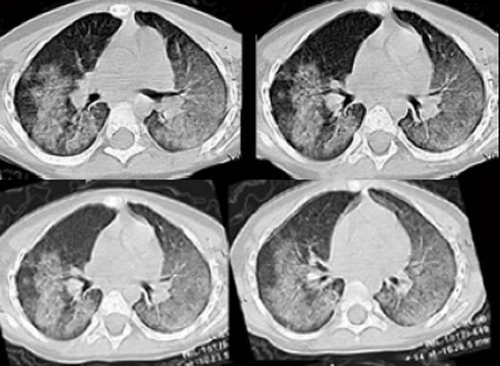

肺部出血是一种很严重的疾病,主要表现为咳血、咳嗽、呼吸困难等,它的病因可能是血管发生破裂或者是凝血功能出现障碍,不过准确的病因还是需要到医院去检查清楚。如果患者有肺部出血的情况,就要注意了,饮食方面也要注意,梨、木耳、百合是润肺的食物,可以吃一点,然后平时的饮食要选择维生素含量高的食物。

肺出血还是能治的,不过要根据患者自身的病况来决定的。要先找到患肺出血的病因,才能对症治疗,病情比较严重的,需要去做手术;如果病情一般的话,那么就要保守治疗。

建议患者要去医院进行检查治疗,如果确诊为肺出血,那么就可能需要住院治疗了,医生可能会用一些消炎药、止血药来治疗,患者要遵医嘱按时服药。在平时要多注意休息,最好是停止工作,先把病情稳定或者痊愈了再去工作,毕竟生命只有一次。